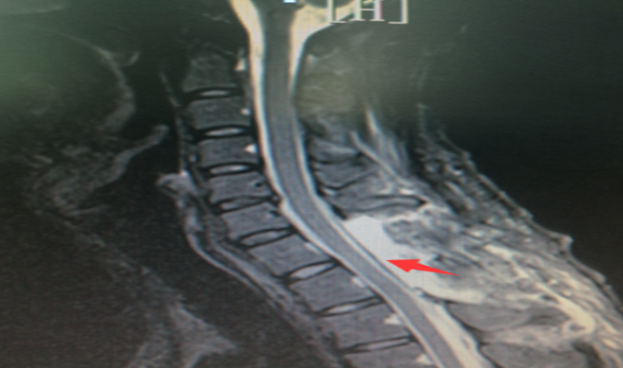

危急三小时 南华医院神经外科专家巧拆颅内定

623x368 - 507KB - PNG